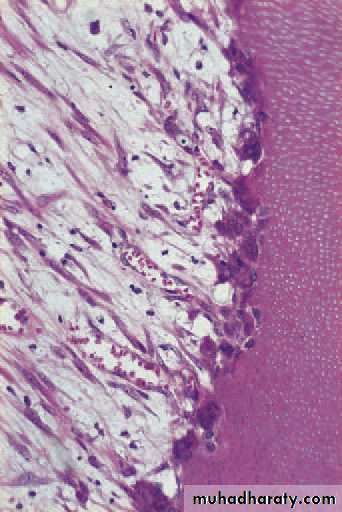

Early acute pulpitis showingthe widely dilated pulp vessels and earlyemigration of leucocytes. There is patchyoedema of the dying odontoblast layer.